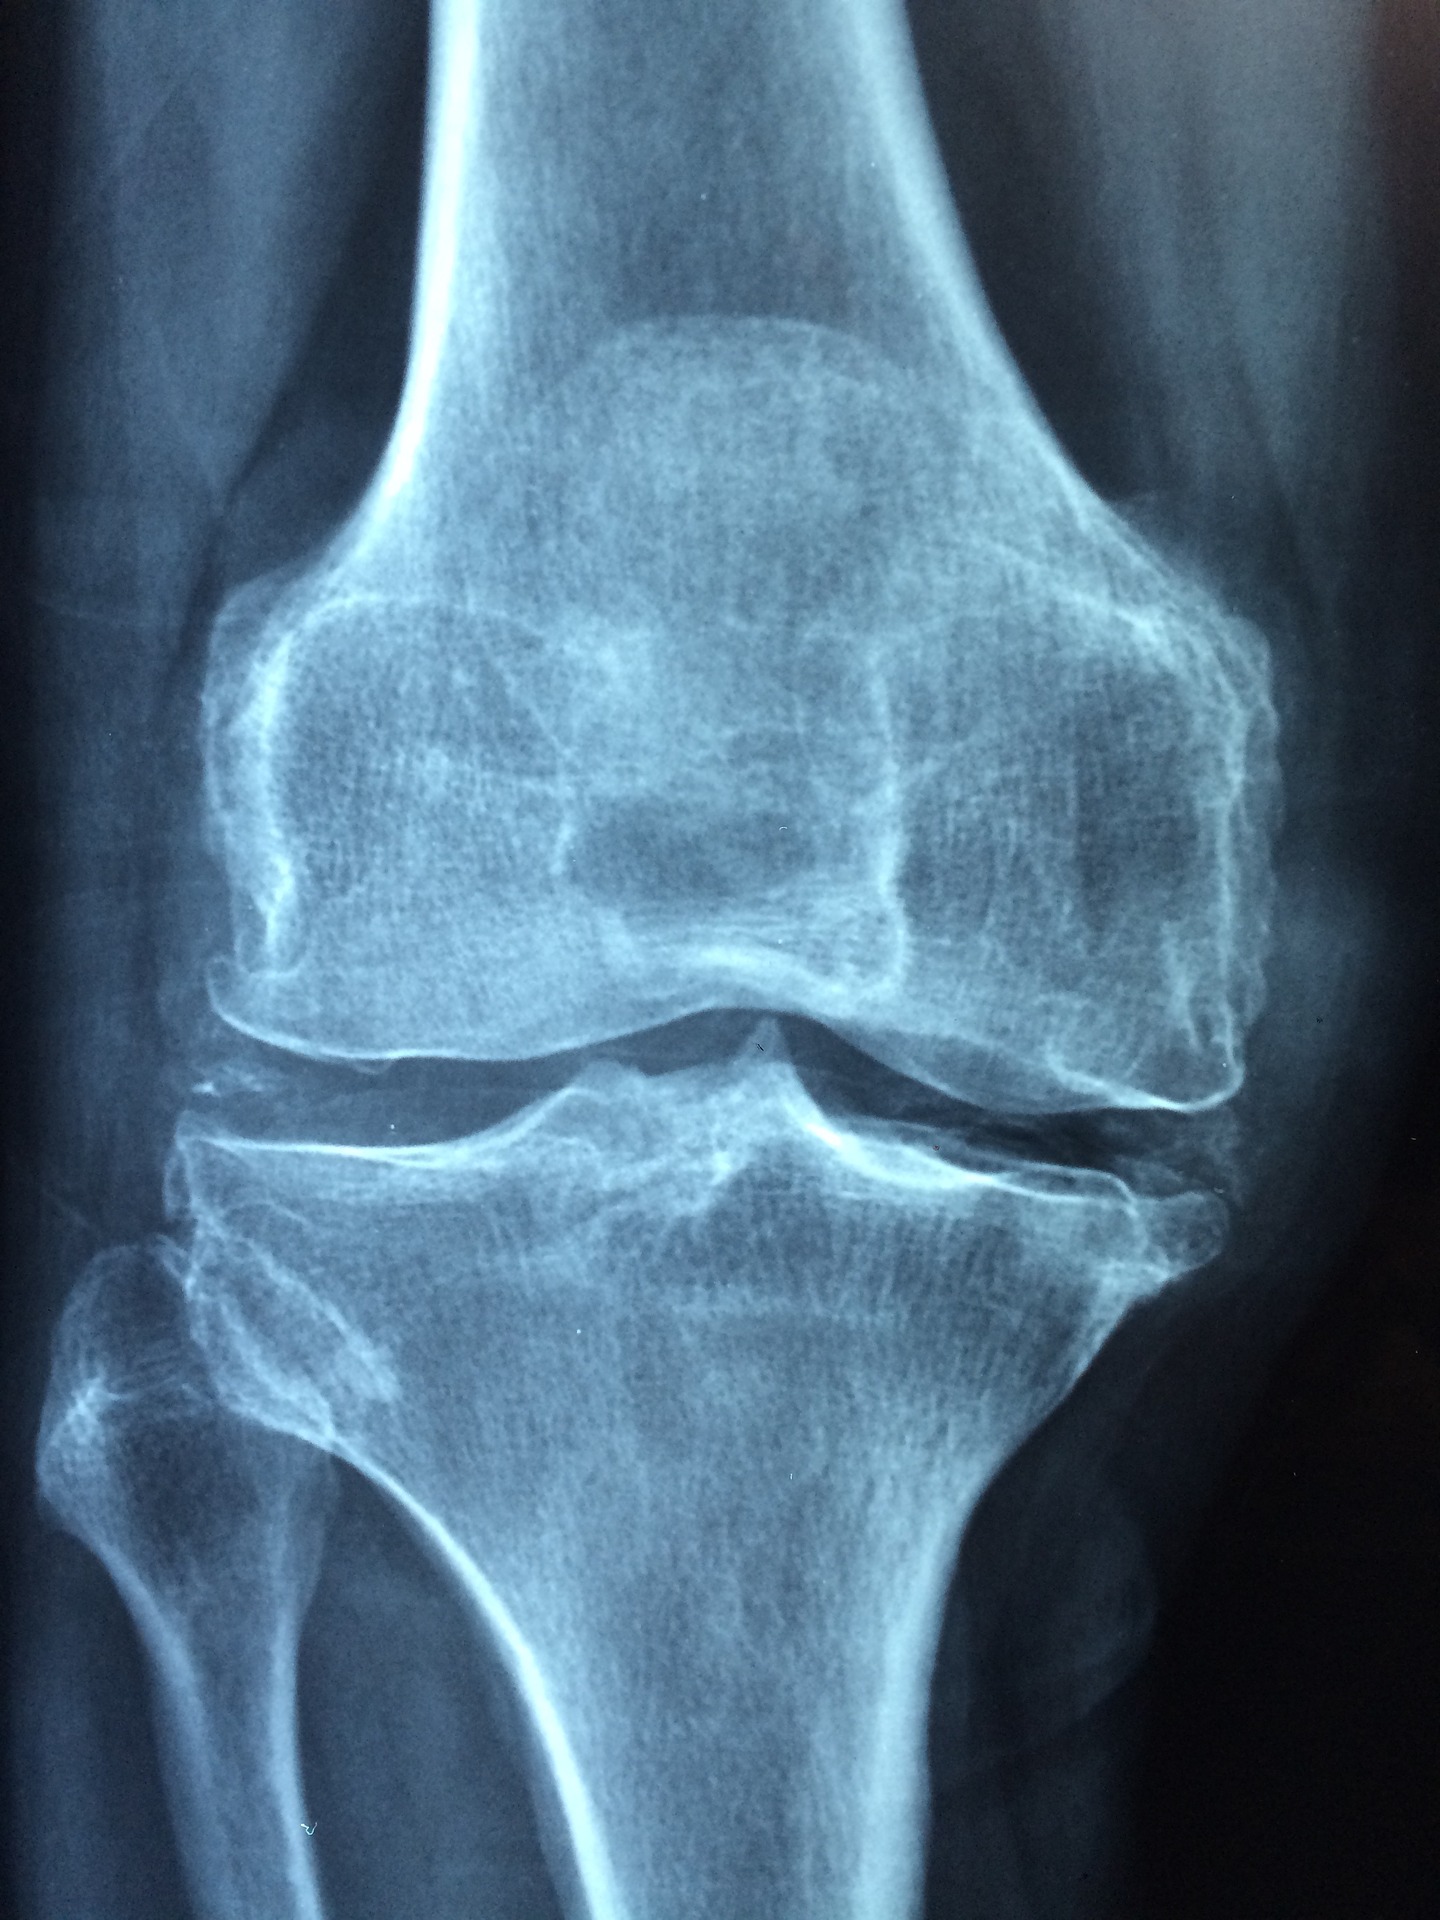

If you’ve ever experienced knee pain, you know how annoying it can be. Whether it’s hampering you from running a 10K, or if it’s causing you pain going up and down stairs, there are people and treatments that can help.

So what is really causing knee pain? The first thing to look at is your body alignment. There is one key assessment that we look for frequently in physical therapy and that is a Q angle. We all generally have a Q angle, but when the angle is larger than it should be, it increases the risk of having knee pain. Women most frequently have larger Q angles because their hips are wider. A larger Q angle places increased stress on the knee. This can happen particularly during dynamic activities (like running, jumping and squatting). Pain results in chronic and repetitive overloading of one side of the knee. Some muscles become too strong and some muscles become too weak. If you have wider hips, you can’t fix your Q angle, but you can decrease knee pain by strengthening some of your muscles that become weak. Usually, the lateral (external) rotators of your hip will become weak. As these muscles get stronger, it allows your hips to be stable during dynamic activities (running, squatting, and jumping) so less stress is placed on the knees. Below are a couple exercises that can help strengthen the lateral rotators.